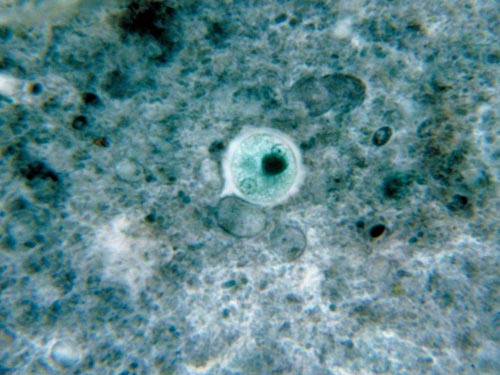

10.痢疾阿米巴

痢疾阿米巴